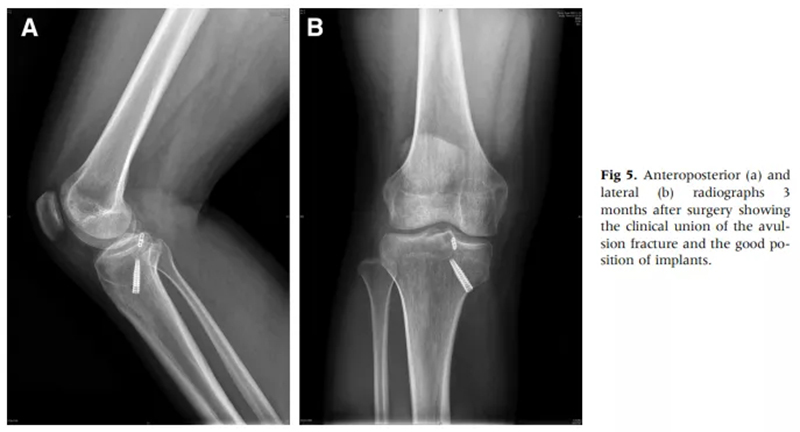

徐醫(yī)附院通過關(guān)節(jié)鏡微創(chuàng)手術(shù),只需做4個8mm左右的小切口,通過做一個直徑0.45cm、長約5cm的骨隧道,將長線環(huán)帶袢鈦板引入關(guān)節(jié)內(nèi),鈦板固定骨折,即可取得很好的穩(wěn)定性,經(jīng)過長時間大規(guī)模的病例累計,形成了40例的總結(jié)分析和評估,系統(tǒng)地講述了關(guān)節(jié)鏡下微創(chuàng)處理后交叉韌帶撕裂的手術(shù)方式、要點和治療效果,對行業(yè)發(fā)展也具有很好的借鑒意義。

術(shù)后第二天即可進(jìn)行功能鍛煉,恢復(fù)快;

內(nèi)固定物無需二次手術(shù)取出。